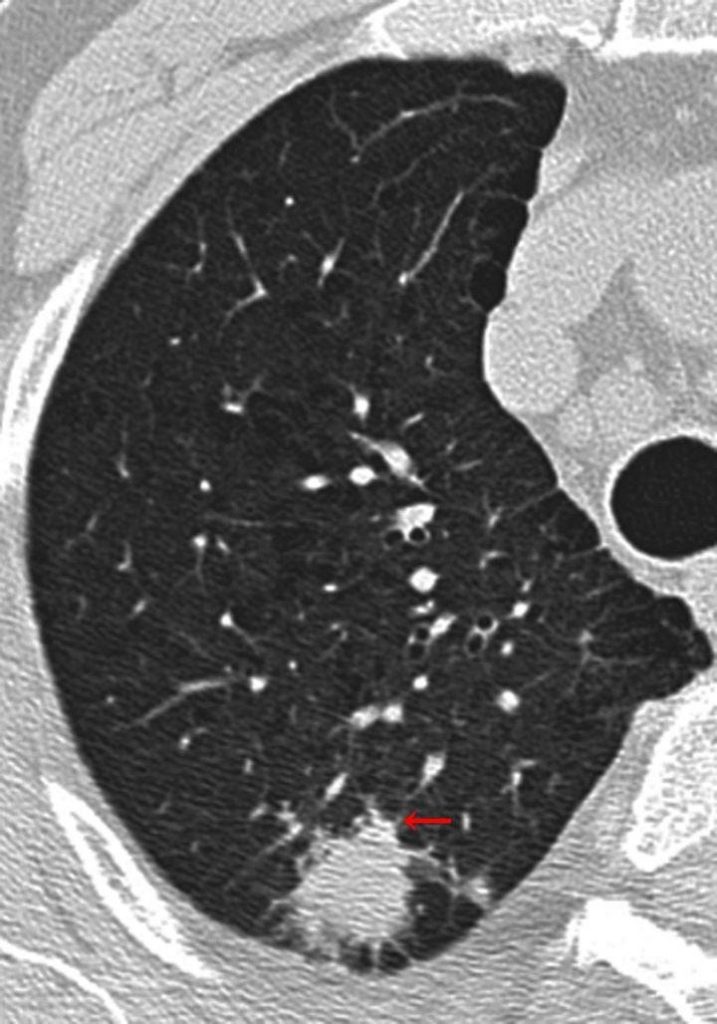

Đính kèm một bức ảnh cho các bạn dễ hình dung nhé! (Ảnh 1)

Trong hình là một khối u phổi ác tính trên hình ảnh CT lồng ngực (chú thích 2). Mũi tên màu đỏ được tác giả Hạnh Lâm Tiểu Thảo thêm vào. Bất thường này trên hình ảnh học được gọi là “dấu răng cưa” (毛刺征), tiếng anh là Spiculation sign (Chú thích 3).

Trong bệnh học, dấu răng cưa thường thể hiện cho sự xâm lấn của khối u ác tính đến các mô xung quanh (Chú thích 4).

Chú thích 2: Ung thư biểu mô tuyến ở phổi (Pulmonary adenocarcinoma).

Chú thích 3: “Dấu răng cưa” thường dùng để mô tả bờ nham nhở xung quanh tổn thương ác tính, gai có thể dài hoặc ngắn, dài thì gọi là “dấu răng cưa dài”, ngắn gọi là “dấu răng cưa ngắn”. Dấu răng cưa ngắn phân bố đều hơn còn được gọi là “dấu vương miện”. Ý nghĩa về bệnh học đằng sau các dấu này không hoàn toàn giống nhau. Mũi tên màu đỏ trong hình chỉ “dấu răng cưa ngắn”.

Lưu ý 4: Ngay cả với “dấu răng cưa ngắn”, ý nghĩa về bệnh học đằng sau nó cũng rất phức tạp, có thể không đơn thuần chỉ sự xâm lấn của khối u mà cũng có thể là thâm nhiễm viêm, tăng sinh mô liên kết dạng sợi,… Do đó, việc vị giảng viên môn chẩn đoán hình ảnh kia bác bỏ việc đổi tên “dấu răng cưa” thành “dấu cự giải” là có lý do cả.